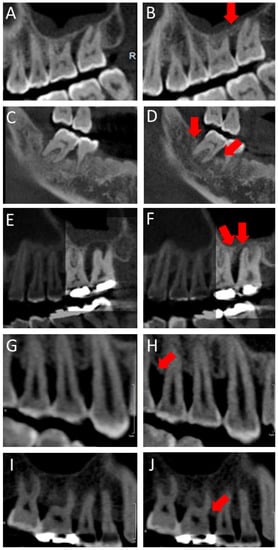

A CBCT scanner (Kodak 9500, Carestream Health, Rochester, NY, USA) was used in this study, providing a grayscale image of 14 bits with a voxel size of 0.2 mm per side. The CBCT images were viewed using 3D imaging software (OnDemand 3D, Cybermed Co., Seoul, Korea). In order to evaluate change of bone height, CBCT images were measured twice before and after treatment on the same site. The cemento-enamel junction (CEJ) was set as an unchanged reference []. If an implant was involved, the reference point was the connection between the abutment and the crown. In the preoperative CBCT image, the distance of the CEJ-base of alveolar bone of the mesial and distal sites of the teeth was measured (Figure 3A–D). To overlap the images of the same cross-section as much as possible before and after treatment, imaginary lines were used (Figure 3E; connecting line of CEJ, A, and D: bone height of first CBCT image, Figure 3F: connecting line of basic point between Figure 3A,D). The distance of the same site after treatment was measured on the second CBCT image (Figure 3A’–D’). The amount of bony change was confirmed by subtracting the first values from the second values (Figure 3A’–D’,A–D). To attest the consistency of the measurements, each section of the CBCT image was assigned a serial number. All pre- and postsurgical bone height measurements were carried out by a single examiner (H.S.C.). A second examiner (J.T.L.) also evaluated bony height at the same serial number image.

Figure 3.

(A–D): The distance between the cemento-enamel junction (CEJ) and base of alveolar bone of the mesial and distal sites on the teeth in the preoperative CBCT image, (E): Connecting line of CEJ, (F): Connecting line of basic point between (A) and (D), (A’–D’): The distance of the same site on the second CBCT image after treatment, (A’–D’): The amount of bony change.

Baseline demographics are summarized in Table 1. There was a significant different bony change between the GTR and Flap groups (p = 0.00001). A total of 1210 subjects of GTR (594 (49.1%) male and 616 (50.9%) female) and 1071 subjects of Flap (666 (62.2%) male and 405 (37.8%) female) were included. Both male and female in the GTR group had smaller bone loss than in the Flap group (p = 0.010 and p = 0.001, respectively). The mean age was 49.8 ± 8.0 (GTR) and 51.3 ± 9.4 (Flap). Significant differences in bony height between GTR and Flap were observed in the 29–45 and 46–53 subgroups (p = 0.00001 and p = 0.040, for each). In GTR group, the 29–45 subgroup had significantly favorable results compared with the 46–53 and 54–76 subgroups (p = 0.0004 and p = 0.006, for each). The non-smoking subjects in the GTR group had higher bone heights than those in the Flap group (−0.09 ± 1.13; GTR and 0.12 ± 0.93; Flap, p = 0.009). The average intervals between the first and second CBCT was 692.7 ± 351.3 days in the GTR group and 688.4 ± 342.9 days in the Flap group. All values of CBCT interval were higher in the GTR subgroups than in the subgroups in Flap (87–490 days: −0.06 ± 1.23, 491–859 days: 0.02 ± 1.24: 860–1543 days: 0.11 ± 1.40 vs. 0.17 ± 0.83, 0.20 ± 1.24, 0.20 ± 0.95). Two subgroups (87–490 and 491–859) had significant differences of bone healing in GTR and Flap (p = 0.0001 and p = 0.018, respectively). With systemic diseases, there was an association between mean heights of alveolar bone of GTR and Flap in hepatitis. Bone height for the Flap group was higher than in the GTR group with significant difference (0.32 ± 0.84: GTR vs. −0.35 ± 0.74: Flap, p = 0.022). No difference was found in other diseases, including hypertension, rhinitis, sinusitis, diabetes mellitus, and hyperlipidemia. In the absence of systemic disease, bone formation was higher in the GTR group than in the Flap group (0.02 ± 1.31: GTR vs. 0.22 ± 1.05: Flap, p = 0.00001). In subjects taking medications for diabetes mellitus and hyperlipidemia, alveolar bone recovery was less in the GTR group than in the Flap group (0.23 ± 0.51: GTR vs. −0.21 ± 0.96: Flap, p = 0.018). However, there was a significantly higher difference for height of bone in the GTR group without medicine than in the Flap group (0.03 ± 1.31: GTR vs. 0.21 ± 1.05: Flap, p = 0.00001). According to oral position, the #14–17, #34–37, and #44–47 subgroups of the GTR group showed higher levels of bone heights than those of the Flap group (0.04 ± 1.21, −0.03 ± 1.10, and −0.03 ± 1.29; GTR vs. 0.32 ± 0.91, 0.18 ± 0.91, and 0.18 ± 1.25; Flap, p = 0.00001, 0.024, and 0.087, respectively). Only the #24–27 group had reverse results of other oral sites (0.10 ± 1.50; GTR vs. 0.07 ± 1.05; Flap, p = 0.342). In all premolars and molars in the GTR group, bone height was higher than that of the Flap group. In particular, it was significantly higher at #4, #5, and #7 (p = 0.033, 0.002, and 0.039, for each) (Figure 4).

Figure 4.

(A–F): CBCT images before and after treatment in the GTR group. (G–J): CBCT images before and after treatment in the Flap group (Arrow: bone healing area).